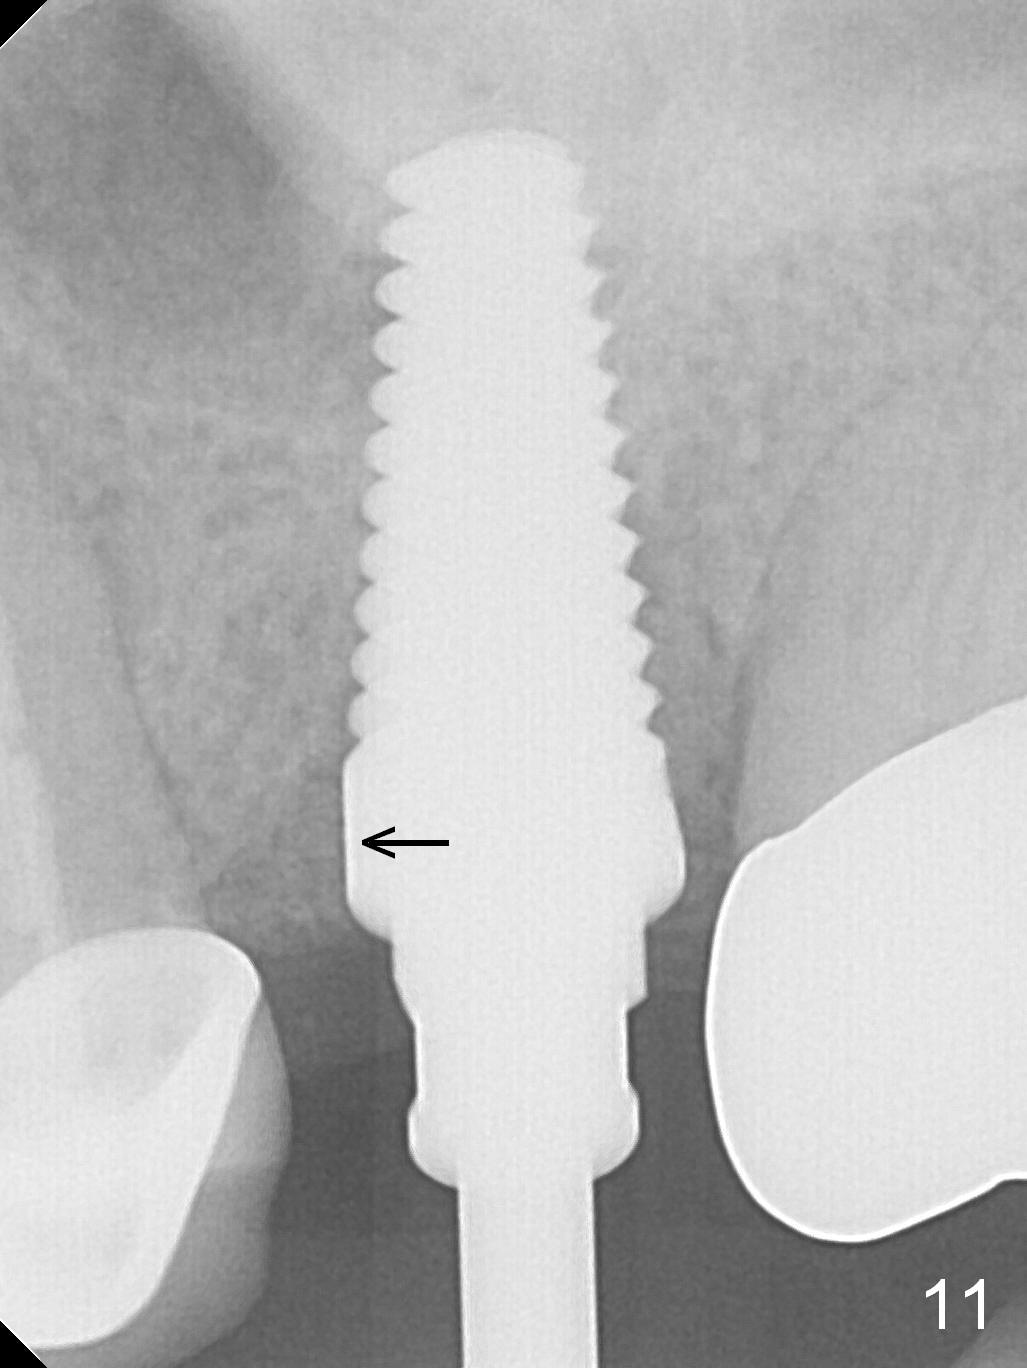

The patient is doing well 9 days postop. The immediate provisional is loose and over-sized. It is removed for trimming and reline; the socket and bone graft (Fig.8 *) are healing. It appears that an angled abutment is required next time of provisional revision. When an angled abutment is being placed 23 days postop (Fig.9), it appears to wiggle the implant due to its long leverage. Instead a healing abutment is placed. The implant is unstable 4.5 months postop with seemingly excessive bone-implant gap (Fig.10 <). The 5.5x9 mm implant is removed. A 5x17 mm tap is used to change the trajectory and sinus lift, followed by 6x17 one (Fig.11). Finally a 6x14 mm tissue-level implant is placed with insertion torque > 50 Ncm (Fig.12; vs. <20 Ncm (Fig.7,10)) and improved trajectory. An immediate provisional is fabricated to prevent the mesial drifting of the tooth #15 (Fig.13 P (*: occlusal clearance)). By using the taps and placing the longer implant, the sinus lift is more obvious (compare Fig.10 and 12 (*)). Sinus lift remains evident 3.5 months postop (Fig.14) with apparently osteointegration (Fig.15).